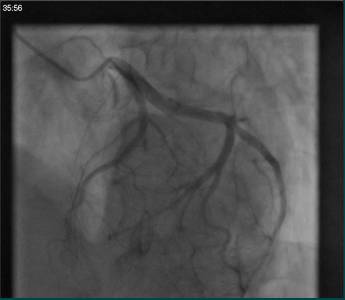

②冠脉造影:

冠脉造影未见明显异常;

⑥冠脉造影(2015.03.02)